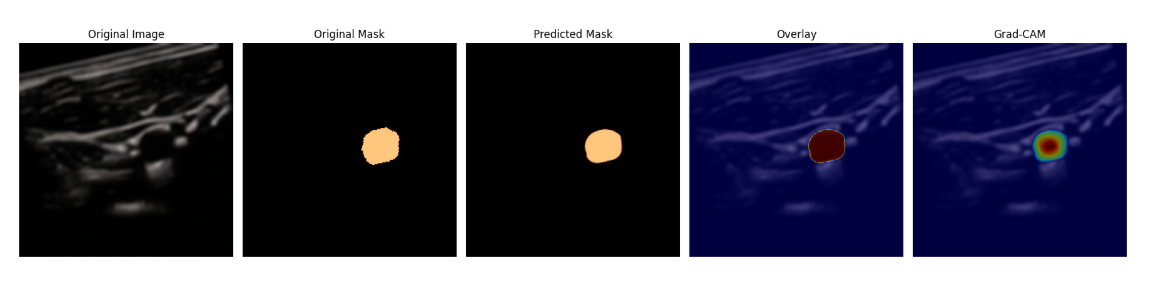

预测的部分结果展示: